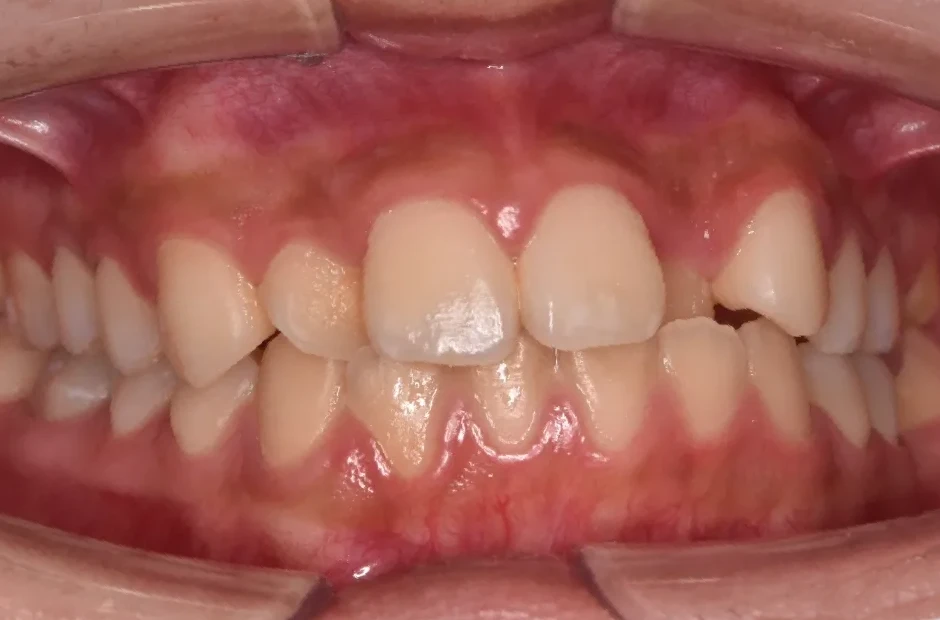

過剰歯

| 診断名・主訴 | でこぼこ |

|---|---|

| 年齢・性別 | 22歳・女性 |

| 治療期間・回数 | 1年6か月 |

| 治療に用いた主な装置 | リンガルブラケット |

| 抜歯部位 | 過剰歯 |

| 治療費 | 100万円(税抜) |

| リスク・副作用 | 装置による違和感・疼痛・歯肉退縮・歯根吸収・虫歯のリスクなど |

治療前